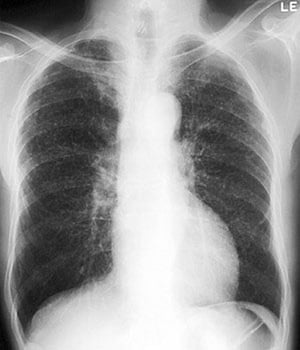

Silicosis—Conglomerate

Image courtesy of David W. Cugell, MD.

Complicated silicosis is characterized by large opacities on chest x-ray or conglomerate opacities with calcifications on chest CT. Imaging shows coalescing of nodules when simple silicosis progresses to complicated silicosis.

Progressive massive fibrosis (PMF, or conglomerate or complicated silicosis) is the advanced form of chronic or accelerated silicosis. It is characterized by widespread masses of fibrosis, typically in the upper lung zones.